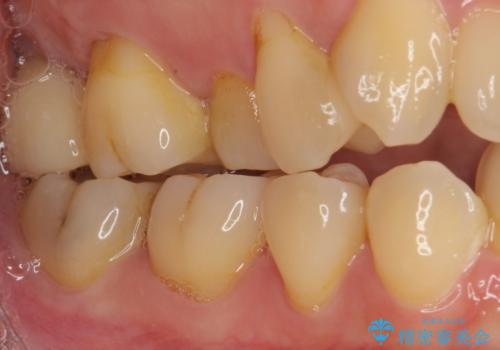

外側を向いている上顎の奥歯は歯ブラシが十分に届かないため、むし歯となるケースが多いのですが、今回むし歯となってしまった歯がそれで、ボロボロになって根だけが残っている状態でした。

患者様と相談し、抜歯をした上でインプラントによる補綴治療を行うこととしました。